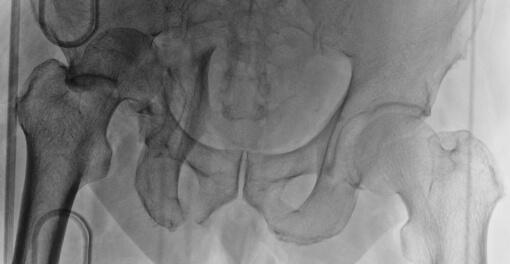

寛骨臼骨折症例

粉砕の強い右寛骨臼骨折の症例。前方・後方アプローチによる観血的整復固定術を行いました。